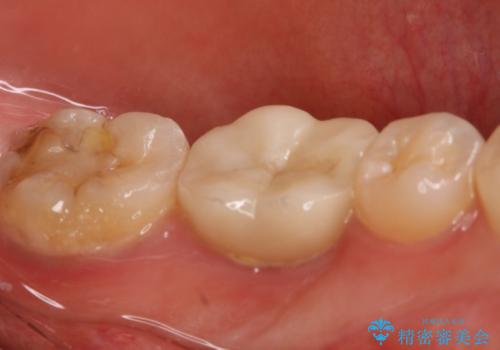

- 左下大臼歯の歯肉に腫れと痛みが繰り返し起こっているので治療を希望し来院された患者様です。

既に治療されている歯でしたが根尖部に病巣が確認出来たので、精密根管治療とクラウンの再治療が必要と判断されました。